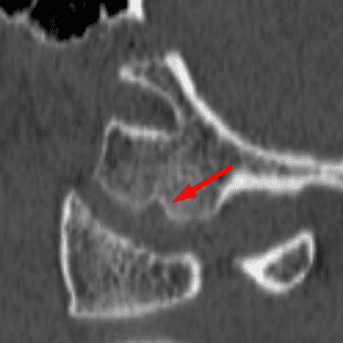

Congenital Anomalies of C1

Case 13